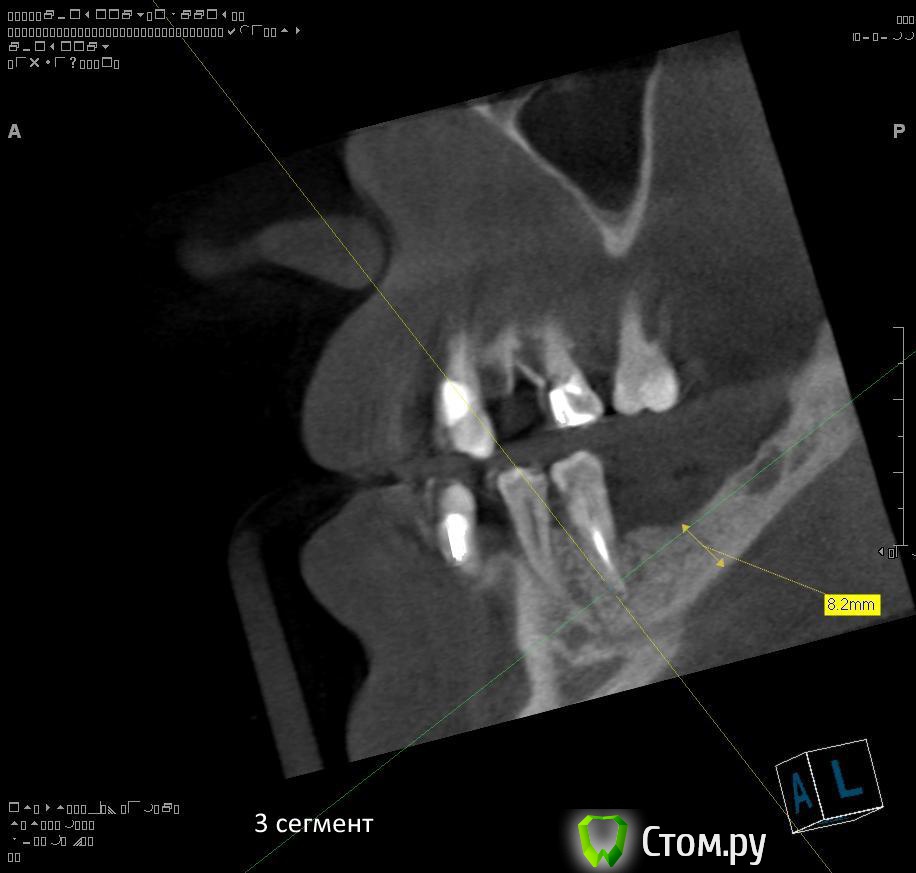

Провели обследование. Ортопед планирует оставить вверху 6 фронтальных зубов (возможно резцы пойдут на удаление), внизу только клыки. Далее последует удаление несостоятельных зубов + иммедиат протезы, продолжение реабилитации.

1. правильно ли я понимаю, что через 1,5 - 2 месяца после удаления 1.4 можно провести аугментацию (синус-лифтинг, латеральное окно, в первом сегменте, возможно с одномоментной установкой имплантатов)?

2. нужна ли в 1 сегменте дополнительная аугментация (по вертикали)?

3. в какие позиции должны быть поставлены имплантаты в 1 сегменте сбоку (1.7, 1.5)?

6. через какой промежуток времени после удаления зубов 3.4, 3.5 проводить аугментацию в 3 сегменте? какая аугментация предпочтительнее? в какие позиции должны быть поставлены имплантаты (3.4, 3.6?)?